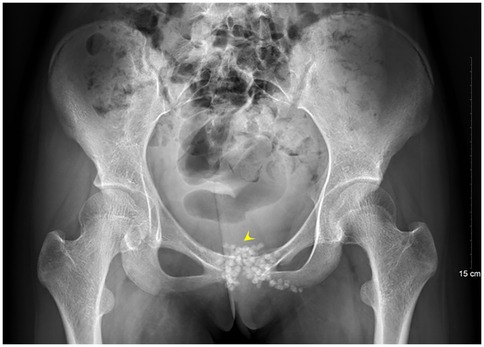

A 13-year-old female presented to the Department of Pediatrics at Dongguan Maternal and Child Health Hospital with a 10-day history of intermittent fever and pain in the pubic symphysis region. The patient denied a history of pelvic surgery, local trauma, or strenuous exercise. Her past medical and family histories were unremarkable. Between February 10 and 18, 2025, she was hospitalized at an external institution due to pubic symphysis pain, restricted lower limb mobility, and high fever. Blood cultures identified the presence of methicillin-resistant Staphylococcus aureus (MRSA) and she was treated initially with cephalosporins and penicillins which resolved the fever but only partially alleviated the pubic pain. Upon transfer to our hospital, physical examination revealed stable vital signs, no fever, localized tenderness and swelling over the pubic symphysis without erythema or fluctuance, bilateral restricted hip motion (aggravated by adduction and abduction), and an antalgic gait. The laboratory findings included a white blood cell count of 6.08 × 109/L (neutrophils: 64.0%), procalcitonin <0.1 ng/ml, and an erythrocyte sedimentation rate (ESR) of 80 mm/h. Blood cultures confirmed the presence of MRSA. Although intravenous antibiotics had resolved the fever, pubic pain and mobility limitations persisted, particularly with limited hip mobility, notably painful external rotation and adduction, where external rotation was less than 15 degrees and adduction was less than 10 degrees. Consultation with orthopedic specialists led to the suspicion of pubic symphysis infection, prompting an MRI examination. The imaging revealed infection of the pubic symphysis with bilateral osteomyelitis and a small abscess in the posteroinferior muscle layer (Figures 1, 2). Based on these clinical manifestations, laboratory results, and imaging findings, the diagnosis was confirmed as pubic symphysis infection with bilateral osteomyelitis and abscess formation.

Figure 1. Preoperative MRI indicates infection of the pubic symphysis.

Figure 2. Preoperative MRI shows infection at the pubic symphysis.